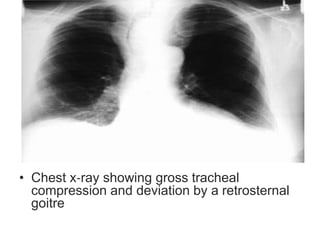

• Chest x‐ray showing gross tracheal

compression and deviation by a retrosternal

goitre

• Chest x‐rayshowing gross tracheal compression and deviation by a retrosternal goitre